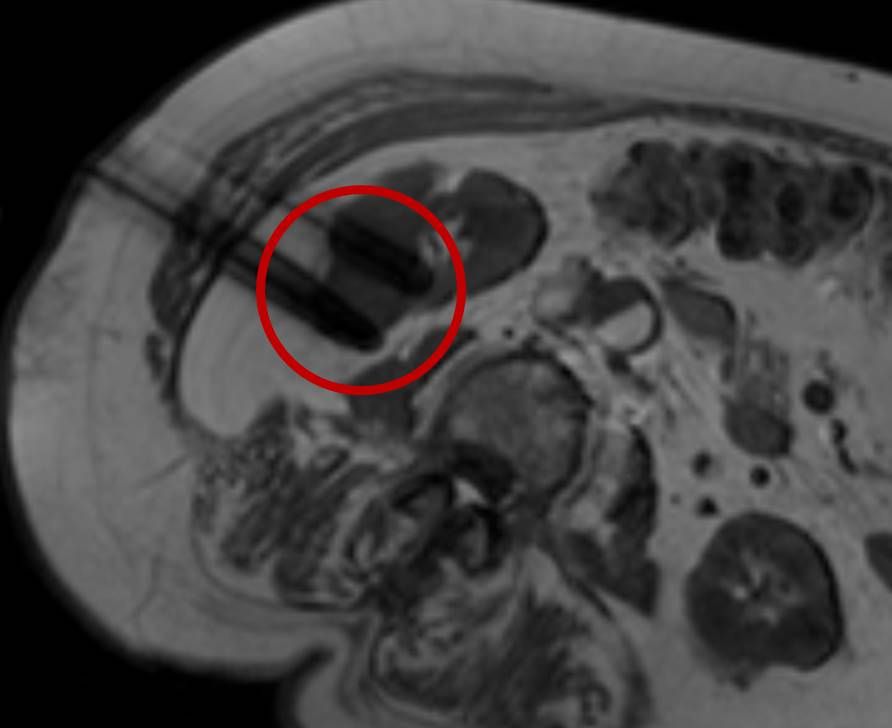

Bei der perkutanen Thermoablation von Nierentumoren werden spezielle Applikatoren unter CT- oder MRT Bildgebung in den Zieltumor eingebracht. Durch Hitze wird der Tumor zerstört.

Abbildung: Bei diesem Patienten wurde ein im Röntgen nur schlecht sichtbarer Knochentumor vor der Operation unter MRT-Kontrolle mit kleinen röntgendichten Spiralen („Coils“) markiert. Damit hat der Operateur eine optimale Darstellung des Tumorbereichs bzw. der Tumorgrenzen und kann gezielter, schonender und effektiver operieren.